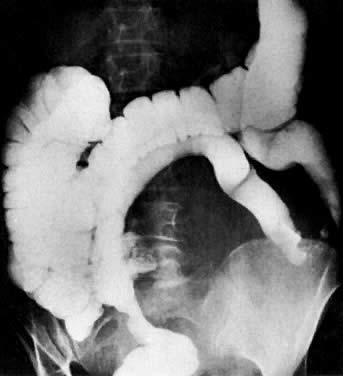

Colon examination shows bowel obstruction (arrow) in sigmoid colon. Patient has advanced endometrial carcinoma.

A 62-year-old woman with cervical cancer. Small-bowel follow-through shows encasement of the distal jejunum (arrow) causing proximal obstruction.

Colon examination shows displacement of the sigmoid colon by a pelvic mass from endometrial carcinoma.